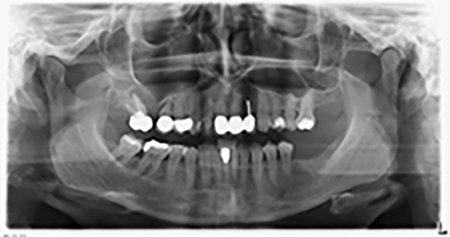

Unos seis meses después de la extracción de las piezas 16 y 14 se realizó una tomografía digital de volúmenes (DVT, Planmeca) para realizar una planificación adecuada y reducir los riesgos al mínimo. En este punto se constató que el hueso no se había regenerado en la cantidad deseada (figuras 2 a 7).

Figuras 2 a 7: Tomografía digital de volúmenes con oferta ósea horizontal reducida.